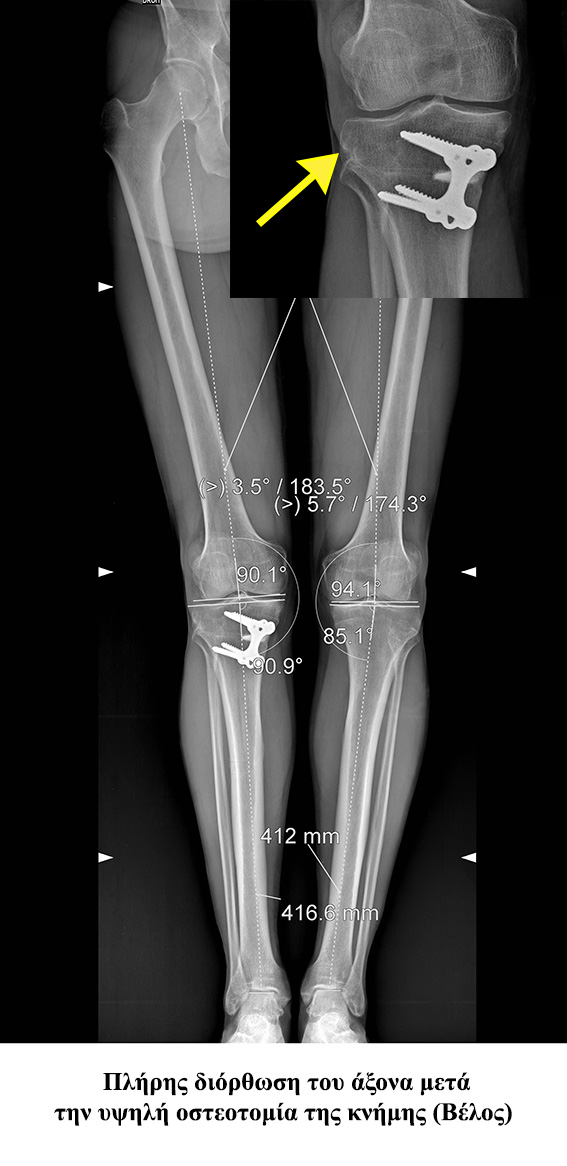

• - Ονομάζεται η απόκλιση του άξονα του γόνατος κατά την οποία η κνήμη και ο μηρός σχηματίζουν γωνία ανοιχτή προς τα έσω. Κατά την παραμόρφωση αυτή τα φορτία του σώματος διέρχονται κυρίως από την έσω πλευρά του γόνατος (έσω μεσάρθριο διάστημα), με αποτέλεσμα αυτό να φθείρεται πιο εύκολα και γρήγορα.

• - Υπάρχει δυνατότητα διόρθωσης πραγματοποιώντας υψηλή οστεοτομία της κνήμης.

• - Πραγματοποιείται οστεοτομία στο άνω άκρο της κνήμης και διόρθωση της παραμόρφωσης του γόνατος

• - Συγκράτηση της διόρθωσης αυτής με τη βοήθεια μικρής πλάκας και κοχλιών.